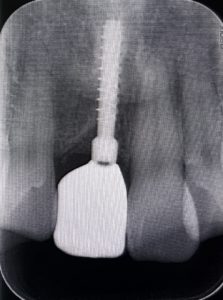

ITインプラントが得意とするのは骨が薄い症例です。特に普通のメーカーでは難しい症例に対して、直径2.2ミリや直径2.8ミリの細いインプラントが使えることです。他のメーカーでは直径3.0ミリが最少となります。

これが何故可能かというと、材質がチタン合金であり通常の純チタンでないので、1.5倍程硬く折れにくいからです。

後は歯茎からの貫通部が細いためにインプラント周囲炎になりにくく、歯茎も下がりにくいという特徴があります。